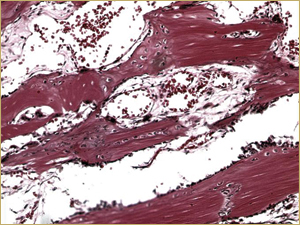

Figure 5b: High-power histologic examination of rabbit maxillary sinus augmented with high-dose (25 mg) bone morphogenetic protein at 2 weeks after procedure. H&E stain, 200× magnification.

There was no difference in appearance between sinuses augmented with low-dose (10 mg) BMP bioimplants (Fig. 5a) and those augmented with high-dose (25 mg) BMP bioimplants (Fig. 5b). Both groups had a high concentration of thin, woven bony trabeculae, which were smaller and more numerous than in sinuses with either autografts or DBM bioimplants.